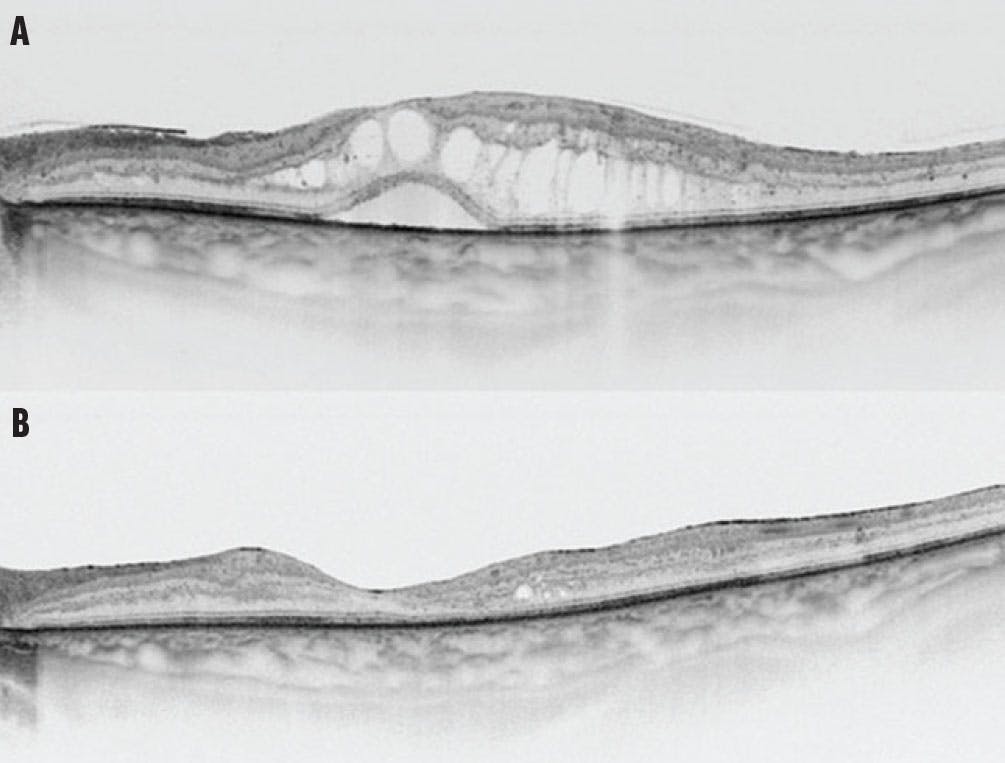

Long-standing DME results in irreversible changes to retinal tissue, especially photoreceptors, making it nearly impossible to achieve visual improvement with delayed treatment. We published a study on treatment-naïve patients who qualified for vitrectomy with internal limiting membrane (ILM) peeling and reported a stable 3-line improvement in visual acuity for 55% of patients, with only 8% of eyes worsening by 1 line in the 48-month postoperative period (Figure 1).5 We hypothesize that these excellent results, which differ significantly from many previous studies, were associated with our inclusion criteria. We included patients with relatively well-controlled diabetes (mean hemoglobin A1c levels were 7.5%) with no prior laser photocoagulation in the macula region, nor anti-VEGF therapy.

<p>Figure 1. Swept-source OCT shows DME before vitrectomy in a 63-year-old woman (A). Postoperatively, OCT imaging of the same patient shows resolution of the DME (B).</p>

Figure 1. Swept-source OCT shows DME before vitrectomy in a 63-year-old woman (A). Postoperatively, OCT imaging of the same patient shows resolution of the DME (B).